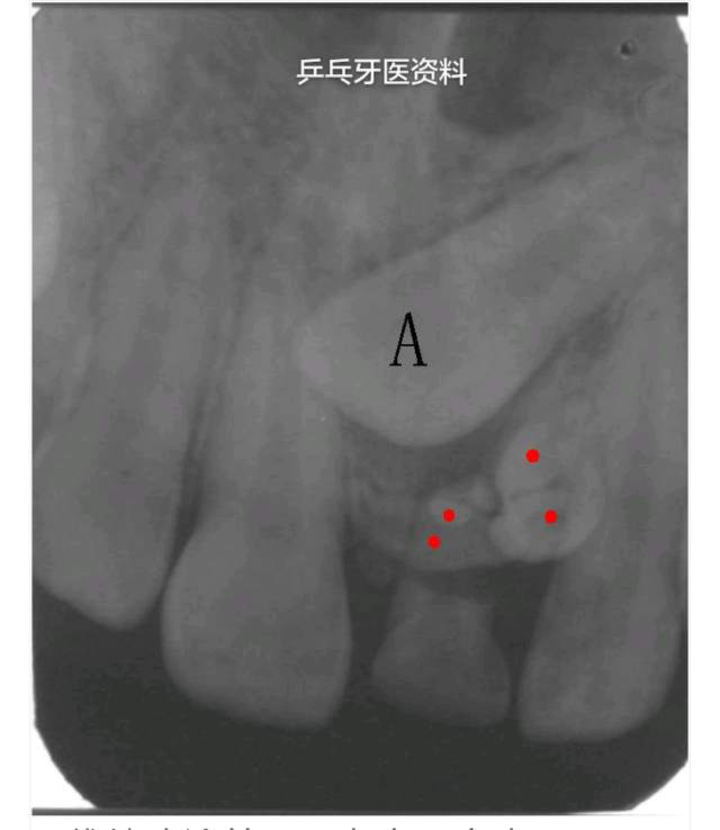

4.颌骨囊肿